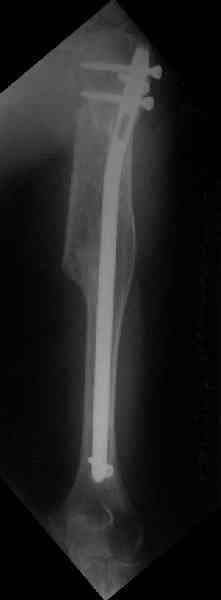

Здесь нет необходимости в серкляже. Вмешиваться на промежуточных отломках приходится, если есть угроза перфорации кожи, или промежуточный отломок попал в фасцию, как пуговица в петлю. В приложении сегментарный оскольчатый перелом плеча в проксимальном отделе, фиксированный больщеберцовым стержнем. Как видите, обошлось без серкляжа. Функция полная.

Александр, великолепные снимки! Вопрос - что за гвоздь?

Это укороченный большеберцовый стержень, которые делает предприятие "ЦИТО".